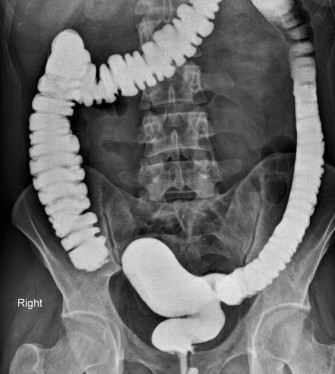

• Syndrome de Turcot

• Article

Le syndrome de Turcot est l'association d'une polypose colique et de tumeurs malignes du système nerveux central. Il s'agit d'une maladie héréditaire à transmission autosomique dominante.

• Syndrome de Lynch

Le syndrome de Lynch est une maladie génétique, caractérisée par une augmentation du risque de développer certains cancers, en particulier le cancer colorectal. Il serait impliqué dans 2 à 3 % des can...